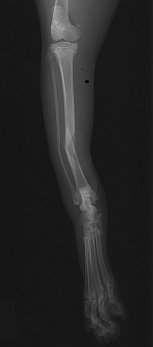

整復前 整復後

高所からの転落により左肩関節を脱臼。鎮静下にて整復→外固定を約2週間実施。